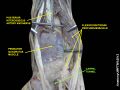

The carpal bones that make up the wrist form an arch which is convex on the dorsal side of the hand and concave on the palmar side. The groove on the palmar side, the sulcus carpi, is covered by the flexor retinaculum, a sheath of tough connective tissue, thus forming the carpal tunnel. On the side of the radius, the flexor retinaculum is attached to the scaphoid bone, more precisely its tubercle, as well as the ridge of trapezium. On the ulnar side, it is attached to the pisiform and hook of hamate.[4]

The tendons of the flexor digitorum superficialis and profundus pass through a common ulnar sheath, while the tendon of the flexor pollicis longus passes through a separate radial sheath. The mesotendon shared by these tendons is attached to the radial and palmar walls of the carpal tunnel.[4]

Superficial to the carpal tunnel and the flexor retinaculum, the ulnar artery and ulnar nerve pass through the ulnar tunnel/Guyon's canal.[4]

The flexor carpi radialis (one tendon) is often incorrectly stated to travel within the carpal tunnel. More precisely, it travels within the fibers of the flexor retinaculum which forms the roof of the carpal tunnel, rather than running inside the tunnel itself.